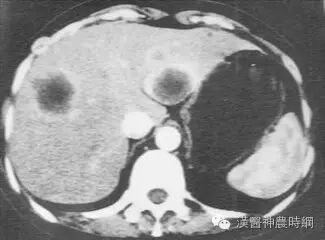

2.计算机X线体层扫描(CT)  CT是一种安全、无创伤、高分辨力的检查方法。对肝癌的定位诊断很有价值。CT能显示肿瘤的大小、位置、数目及与周围脏器和大血管的关系,可检出1cm左右的早期肝癌。并有助于了解是否伴发肝外转移,如肝门淋巴结,胰头后淋巴结等。结合增强扫描可以判断病变的性质,对肝癌与肝血管瘤的鉴别有较大的价值。平扫下肝癌多为低密度占位,边缘清晰或模糊,部分有包膜的肝癌可显示晕圈征。较大的肝癌可见更低密度的坏死区,少数肝癌可见钙化。增强扫描有滴注法、大剂量推注、推注加动态扫描等。

肝癌在动脉期尤以注药20s内强化最为明显,癌灶密度高于周围肝组织。30~40s后造影剂进入细胞间隙转入实质期,病灶又恢复为低密度,显示更为清晰。近将肝动脉造影与CT检查相结合,开展CT动脉造影(CTA)和CT动脉门脉造影(CTAP),对提高小肝癌的检出率有一定价值。也有人在CT检查前一周经肝动脉插管注入碘化油(lipiodo1),再做CT扫描,这种lipiodol-CT可检出0.5cm的小肝癌。对于<1cm的肝癌,Uchida报告US、CT、肝动脉造影和几种CT检查的分辨力为:US 63%、普通CT 12%、滴注法增强扫描65%、CTA 71%、CTAP 80%、lipiodol-CT 89%。